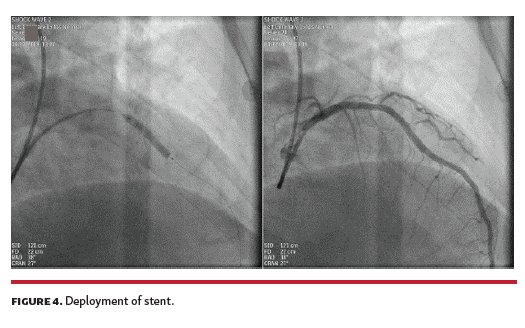

A 62-year-old man with a history of insulin-dependent diabetes mellitus, peripheral arterial disease, hypertension, and dyslipidemia presented to the emergency room with acute chest pain of 2-hour duration. Electrocardiogram revealed ST elevation in precordial leads (Figure 1A). He underwent emergency coronary angiogram, which revealed total occlusion of the proximal left anterior descending (LAD) coronary artery (Figure 1B). Using a transradial 6 Fr EBU 3.5 guide, a floppy wire passed to the distal part of the LAD (Figure 1C).